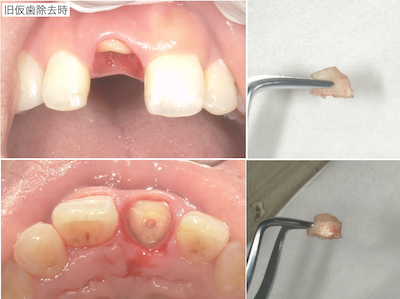

コンポジットレジンで歯冠部が作られていました。歯肉縁下まで及んでいたので、いったん全て外して、状況を確認した方が良いことを説明しました。患者さんも歯肉のラインが気になっておられ、前歯の形も理想ではないとのことだったので、全て外して仮歯の作成を行うことを説明し、同意頂けました。

旧仮歯を撤去したところ、歯根が一部水平的に破折していました。歯肉のラインが歪になっていたのはこのことが原因であったと説明しました。支台築造を行い、仮歯を作成しました。患者さんはホワイトニングを希望しておられたので、ホームホワイトニングを行ったのちに周りの歯の色に合わせてセラミック冠を作成することで同意頂いたので、ホームホワイトニングを行いました。